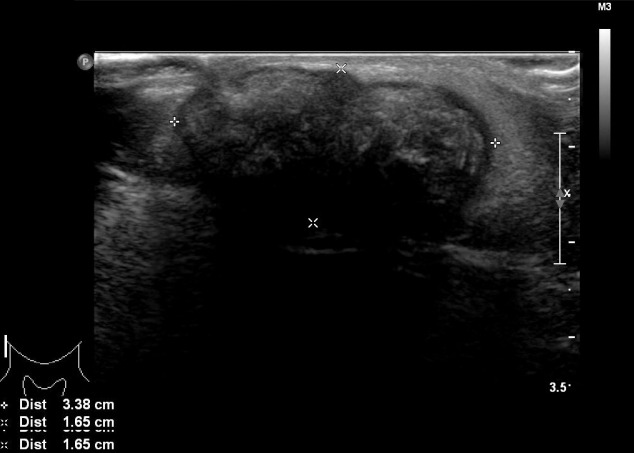

诊断时为35岁的张雨绮(女,化名)右侧腮腺区有肿块,就诊于佳学基因检测合作医院的整形外科。 肿块直径约 1 cm,张雨绮因无临床症状而拒绝手术切除。 然而,在怀孕的中晚期,肿块的大小增加到 5 厘米(图 1),并且变得疼痛。 分娩后肿块停止生长。 触诊肿块时,患者报告疼痛从腮腺区放射至耳后区。 病灶摸起来温暖、坚硬、淡蓝色和分叶状。 由于临床症状加重,患者同意接受手术切除肿块。

毛母质瘤是一种良性皮肤肿瘤,起源于分化为毛母质细胞的表皮原始基底细胞。 大多数毛母质瘤的直径约为 1 厘米,而直径为 5 厘米或以上的则被归类为巨大毛母质瘤。 头颈部毛母质瘤的鉴别诊断包括皮脂腺囊肿、骨化性血肿、鳃残余、耳前窦、淋巴结肿大、巨细胞瘤、软骨瘤、皮样囊肿、退化性纤维黄瘤、异物反应、皮肤骨瘤。 准确诊断毛母质瘤需要放射影像学和组织病理学检查。 其组织病理学特征包括外围的细胞簇(包括有核基底样细胞)和中心的无核影细胞(也称为“鬼细胞”)呈圆形排列。 巨大的毛母质瘤通常与外伤有关,并且有时会在外伤事件后观察到溃疡或坏死组织物质的局灶性经表皮消除。

在本报告中,我们描述了一名 34 岁女性在右侧腮腺区域患有巨大毛母质瘤的病例。 最初发现肿块时,直径为 1 厘米,无症状。 然而,在患者怀孕期间,肿块长至 5 厘米并出现症状。 患者称,最初检测到肿块后右侧腮腺区域未发生外伤。